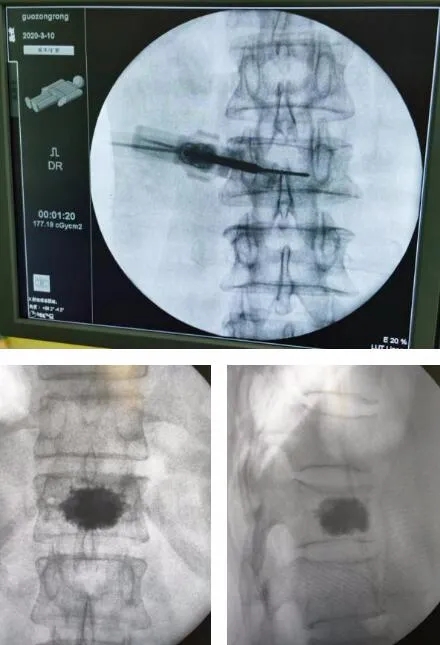

6Šťł22ŠŚą��´╝îňżÉňĚ×ń╗üŠůłňî╗ÚÖóŔäŐŠč▒šžĹň揊ČíńŻ┐šöĘňĄęšÄĹ?ڬʚžĹŠëőŠť»Šť║Šó░ń║║��´╝îń╣ÉŠłÉńŞ║ńŞÇňÉŹ76ň▓üšÜäŔ⪊ĄÄňÄőš╝ęڬʊ՜ŠéúŔÇůň«îŠłÉŠÖ║ŔâŻňż«ňłŤŠĄÄńŻôŠłÉňŻóŠť»����ŃÇéŔ┐ÖňĚ▓Šś»ń╗üŠůłňî╗ÚÖóŔäŐŠč▒šžĹńŞÇňĹĘňĄÜŠŚÂÚŚ┤ň«îŠłÉšÜäšČČ9ňĆ░ڬʚžĹŠť║Šó░ń║║Šîçň»╝ńŞőŠĄÄńŻôŠłÉňŻóŠëőŠť»����ŃÇé

ŠëőŠť»Šť║Šó░ń║║ń╗ąŠÖ║Ŕ⯊ť║Šó░ŔçéńŞ║ňč║šíÇ��´╝îŠĘíŠőčš╗ƚܫڬʊ░┤Š│ąŠĄÄńŻôŠłÉňŻóŠť»šÜ䊾ŻŠť»ňŐ׊│Ľ��´╝îńŞżŔíÄńŻôŠłÉňŻóŠť»ň«ÜńŻŹń╗ąňĆŐڬʊ░┤Š│ąŠĄŹňůą��´╝îŔ«ęŠëőŠť»Ŕ«żŔ«íš▓żňçćŠîçň»╝ŠëőŠť»ň«×Ú¬î��´╝îň╝ÇňłŤń║ćŔäŐŠč▒ňĄľšžĹŠľ░ŠŚÂń╗ú����ŃÇéÔÇťňĄęšÄĹ?ڬʚžĹŠëőŠť»Šť║Šó░ń║║š│╗š╗čšö▒Šť║Šó░ŔçéńŞ╗Šť║ŃÇüňůëňşŽŔĚčŔެš│╗š╗čŃÇüńŞ╗ŠÄžňĆ░ŔŻŽš╗䊳É����ŃÇéň«âŔâŻňçşŔ»üŠť»ňëŹňŽäŠâ│ŔĚ»ňżä��´╝îŔç¬ňŐĘŔ░âšÉćŔ┐ŤÚĺłŔžĺň║ŽŃÇüší«ň«Üň«ÜńŻŹšé╣��´╝îň╣ŠÖ║ŔâŻŔç¬ňŐĘň»╗Šëż����ŃÇéŔ»ąÚí╣ŠÖ║Ŕ⯊ëőŔë║šÜäň║öšöĘňĄžňĄžŠĆÉÚźśń║ćŠëőŠť»š▓żňçćň║Ž��´╝îÚĽîŠ▒░ÚÇĆŔžćŠČ튼░ń╗ąňĆŐŠëőŠť»ňŹ▒ň«│šÜäšłćňĆĹ����ŃÇéÔǣڬʚžĹňĄžńŞ╗ń╗╗ŃÇüń╗üŠůłňî╗ÚÖóŔÉąńŞÜňë»ÚÖóÚĽ┐ňůłň«╣Ŕ»┤����ŃÇé76ň▓üŔÇüń║║Ŕ⪊ĄÄڬʊ՜��´╝║Šó░ń║║ňŐęňŐŤ��´╝»ňÉÄńŞĄňĄęňç║ÚÖóŠéúŔÇůŠś»ň«ÂńŻĆÚé│ňĚךÜä76ň▓üňşčňĄžšłĚ��´╝îńŞÇńެŠťłňëŹ��´╝îŔÇüń║║ňťĘň«ÂŠÉČÚ珚ëꊌŠĹöňÇĺ��´╝îšľ╝šŚŤńŞąÚçŹńŞŹňĆ»Š┤╗ňŐĘ��´╝îňťĘň«ÂňŹžň║ŐńŞÇŠťłŠ▓튝ëš╝ôŔžú��´╝îŔóźň«Âń║║ÚÇüŠŁąňżÉňĚ×ń╗üŠůłňî╗ÚÖóŠ▓╗šľŚ��´╝îš╗ĆŠúÇŠčąŔ»ŐŠľşńŞ║ÔÇťŔâŞ12ŠĄÄńŻôňÄőš╝ęŠÇžÚ¬ĘŠŐśÔÇŁ��´╝îŠëőŠť»ŠîçňżüŠśÄší«��´╝îÚťÇŔŽüńŞżŔíÄńŻôŠłÉňŻóŠť»����ŃÇé

ńŞÄŠéúŔÇůňĆŐň«Âń║║ńŞżŔíŞňÉîňÉÄ��´╝îŠÇŁÚçĆňł░ŠéúŔÇůňĚ▓76ň▓üÚźśÚżä��´╝îŔç¬ňĚ▒ŠéúŠťëŔů░ŠĄÄÚŚ┤šŤśš¬üňç║��´╝îŔů░ŠĄÄÚÇÇŔíîŠÇžŠö╣ňĆś��´╝îŔ┐śŠéúŠťëŠÖÜň╣┤ń║║šÜäńŞÇń║Ťňč║šíÇšŚů��´╝îŠëőŠť»ňŹ▒ň«│ŔżâňĄž��´╝îň╝áňćÂňî╗ňĄľŔí»ňŤóÚśčŔüöňÉłňćůšžĹŃÇüÚ║╗Úć뚞ŚŁüň╝ÇŠť»ňëŹŔ«ĘŔ«║��´╝îň«íŠůÄŔ»äń╝░ŠëőŠť»ŠŞůÚŁÖ��´╝îší«ň«ÜńŻ┐šöĘňĄęšÄĹ?ڬʚžĹŠëőŠť»Šť║Šó░ń║║ńŞżŔíÄńŻôŠłÉňŻóŠť»šÜäŠëőŠť»Ŕ«íňłĺ��´╝îň╣ÂňłÂŔ«óŠťÇń╝śňëőŠť»ňŐ׊│Ľ��´╝îší«ň«Üń║抝»ńŞşš╝ęščşŠëőŠť»ŠŚÂÚŚ┤��´╝îňůůňłćňĄŹńŻŹ��´╝îÚóäÚś▓ڬʊ░┤Š│ąŠŞŚŠ╝ĆšłćňĆĹ��´╝»ňÉÄÚóäÚś▓šćĆŠčôšşëńŞÇš│╗ňłŚŠşąń╝É����ŃÇé6Šťł22ŠŚą��´╝îňşčňĄžšłĚšÜ䊥ÄńŻôŠłÉňŻóŠëőŠť»ńŞżŔíî����ŃÇéŠëőŠť»ňî╗šöčňůłŔúůšŻ«3Dň»╝Ŕł¬Šť║Šó░ń║║šĄ║ŔެňÖĘ��´╝îÚÇĆŔžćň«ÜńŻŹŔâŞ12ŠĄÄńŻô��´╝îŔíî3DŠłÉňâĆ��´╝îŠĘíŠőčŔâŞ12ňĚŽńżžŠĄÄň╝ôŠá╣šę┐ňł║��´╝îňťĘň«ÜńŻŹšé╣ňüÜńŞÇÚĽ┐š║Ž0.5ňÄśš▒│ňłçňĆú��´╝îÚÇÜŔ┐çň»╝Ŕł¬Šť║Šó░ń║║ňąŚšşĺń║ÄŔâŞ12ňĚŽńżžŠĄÄň╝ôŠëôňůąň»╝Úĺł��´╝┤Ŕç│ŠŐÁŔżżŠĄÄńŻôňÉÄ1/4ňĄä��´╝┐ŠŹóڬʊ░┤Š│ąń║őŠâůňąŚš«í��´╝îÚÇÜŔ┐皯«ňůąšÜäڬʊ░┤Š│ąŠ│ĘňůąňÖĘňťĘÚÇĆŔžćńŞőš╝ôŠůóŠ│Ęňůąňíźňůůš║Ž2mlڬʊ░┤Š│ą��´╝îňżůŔÁĚŠ║ÉňçŁňŤ║ňÉÄň揊ČíŠ│Ęňůą2mlڬʊ░┤Š│ą��´╝îší«ň«ÜŠĄÄńŻôÚźśň║ŽŠüóňĄŹńŞöŠŚáŠśżšŁÇڬʊ░┤Š│ąňĄľŠ║ó��´╝ÇňÉÄňĆľňç║Ú¬ĘňíźňůůŔúůšŻ«����ŃÇéŠëőŠť»ńŞŹňł░1ň░ĆŠŚÂÚí║Úüéšźúń║ő����ŃÇé6Šťł24ŠŚą��´╝»ňÉÄńŞĄňĄę��´╝îŠüóňĄŹń╝śň╝éšÜäňşčňĄžšłĚňŁÉňťĘň║ŐŔż╣ŠľÖšÉć��´╝îňçćňĄçňç║ÚÖóňŤ×ň«Âń║ć����ŃÇé

ŠÖ║Ŕ⯠š▓żňçć ňż«ňłŤÔÇöÔÇöňĄęšÄĹڬʚžĹŠëőŠť»Šť║Šó░ń║║ňĄęšÄĹ?ڬʚžĹŠëőŠť»Šť║Šó░ń║║ŔżůňŐęňî╗šöčňçćší«ň«ÜńŻŹŠĄŹňůąšëꊳľŠëőŠť»ňÖĘŠó░��´╝îň░ĄňůÂň»╣ňż«ňłŤŠť»ň╝ĆŃÇüÚźśňŹ▒ň«│ňî║ňččňůĚŠťëŠśżšŁÇń╝śňŐ┐��´╝îňĆ»ŠťëšöĘÚÖŹńŻÄŠëőŠť»ňŹ▒ň«│ŃÇüÚĽîŠ▒░ŠëőŠť»ň╣ÂňĆĹšŚç����ŃÇéňłźšÜä��´╝îň«âň░ÜŠťëńŞÇńެŠśżŔĹŚń╝śňŐ┐´╝Üňč║ń║ÄŠť║Šó░ń║║šÜäŠôŹńŻťŠÁüšĘő��´╝îń╗ůÚťÇŔŽüňťĘŠť»ňëŹŃÇüň«ÜńŻŹň»╝ÚĺłŔ┐ŤňůąňÉÄŃÇüŔ×║ÚĺëŔ┐ŤňůąňÉÄšşë3ńެšÄ»ŔŐéŔÄĚňĆľňŤżňâĆ��´╝îXň░äš║┐ŔżÉň░äŠÇ╗ÚçĆňĄžň╣ůň║ŽÚÖŹńŻÄ����ŃÇéňťĘŔÄĚňĆľňŤżňâĆňÄćšĘőńŞş��´╝║Šó░ń║║ŠëőŔçéšĘ│ňŤ║ŠŐŐŠîüňÖĘŠó░ňĺŹňůąšëę��´╝îňî╗ŠŐĄŔüîňĹśŠŚáÚťÇŔóĺÚť▓ňťĘXň░äš║┐ňî║ňčč��´╝ëšöĘÚÖŹńŻÄňî╗ŠŐĄŔüîňĹśXň░äš║┐ŠŹčň«│����ŃÇé

Š▒čŔőĆšČČń║îňĆ░ÔÇťňĄęšÄĹÔǣڬʚžĹŠť║Šó░ń║║ňĚ▓ŔÉŻŠłĚń╗üŠůłňżÉňĚ×ń╗üŠůłňî╗ÚÖó2019ň╣┤11ŠťłńŞşŠŚČň╝ĽŔ┐ŤŠ▒čŔőĆšťüšČČń║îňĆ░ňĄęšÄĹ?ڬʚžĹŠëőŠť»Šť║Šó░ń║║��´╝î5ńެŠťłŠŚÂÚŚ┤ڬʚžĹ9ńެšŚůňî║ňů▒ň«îŠłÉŠť║Šó░ń║║Šîçň»╝ńŞőŠëőŠť»131ńżő��´╝îňîůŠőČŔâŞŔů░ŠĄÄڬʊ՜ŠĄÄńŻôŠłÉňŻóŠť»��´╝îš╗ƚܫÚĺëŠúĺňćůšëóڣኝ»��´╝îŔéíÚ¬ĘÚółÚ¬ĘŠŐśňŐáňÄőŔ×║ÚĺëšëóÚŁá��´╝îń╗ąňĆŐŔłčÚ¬Ęڬʊ՜Ŕ×║ÚĺëšëóÚŁáŃÇüŔéíÚ¬ĘňĄ┤ňŁĆŠş╗ňçĆňÄőŠĄŹÚ¬ĘŃÇüŔâźÚ¬Ęň╣│ňĆ░ڬʊ՜ňŐáňÄőŔ×║ÚĺëšëóÚŁáŃÇüŔĚčÚ¬ĘŔĚŁÚ¬Ęڬʊ՜Ŕ×║ÚĺëšëóÚŁáŃÇüÚ¬ĘŔé┐šśĄŠ┤╗ŠúÇšşëŠëőŠť»����ŃÇéňĄęšÄĹ?ڬʚžĹŠëőŠť»Šť║Šó░ń║║ń╗ąň«âň╝║šŤŤšÜäňůëňşŽŔ┐ŻŔެš│╗š╗čňĺîŠôŹńŻťšĘ│ňŤ║šÜ䊝║Šó░Ŕçé��´╝îŔÁäňŐęڬʚžĹňî╗šöčš▓żňçćň«îŠłÉŠëőŠť»��´╝îňĄžňĄžŠĆÉÚźśń║ćŠëőŠť»ňçćší«ň║Ž��´╝îÚÖŹńŻÄń║ćŠëőŠť»ňŹ▒ň«│����ŃÇéňĄęšÄĹڬʚžĹŠëőŠť»Šť║Šó░ń║║šÜäň╝ĽŔ┐Ť��´╝îń╗úŔíĘŠłĹÚÖóŠÖ║ŠůžÚ¬ĘšžĹň╗║Ŕ«żňĆłŔ┐łňç║ń║ćňŁÜň«×šÜäńŞÇŠşą����ŃÇ銾皟áŠ│ëŠ║É´╝ÜňżÉňĚ×ń╗üŠůłňî╗ÚÖó